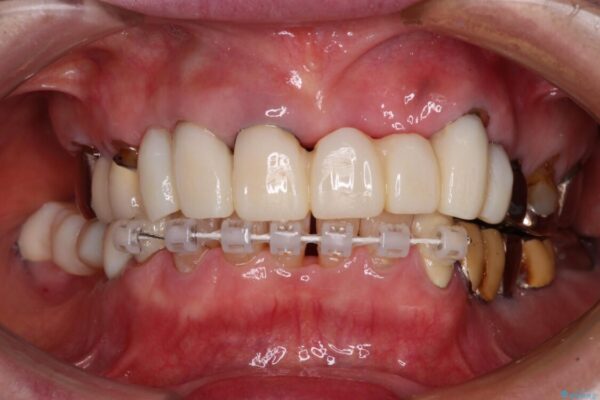

治療途中

• 前歯をきれいにしたい インプラントや部分矯正を用いた総合歯科治療 治療途中画像